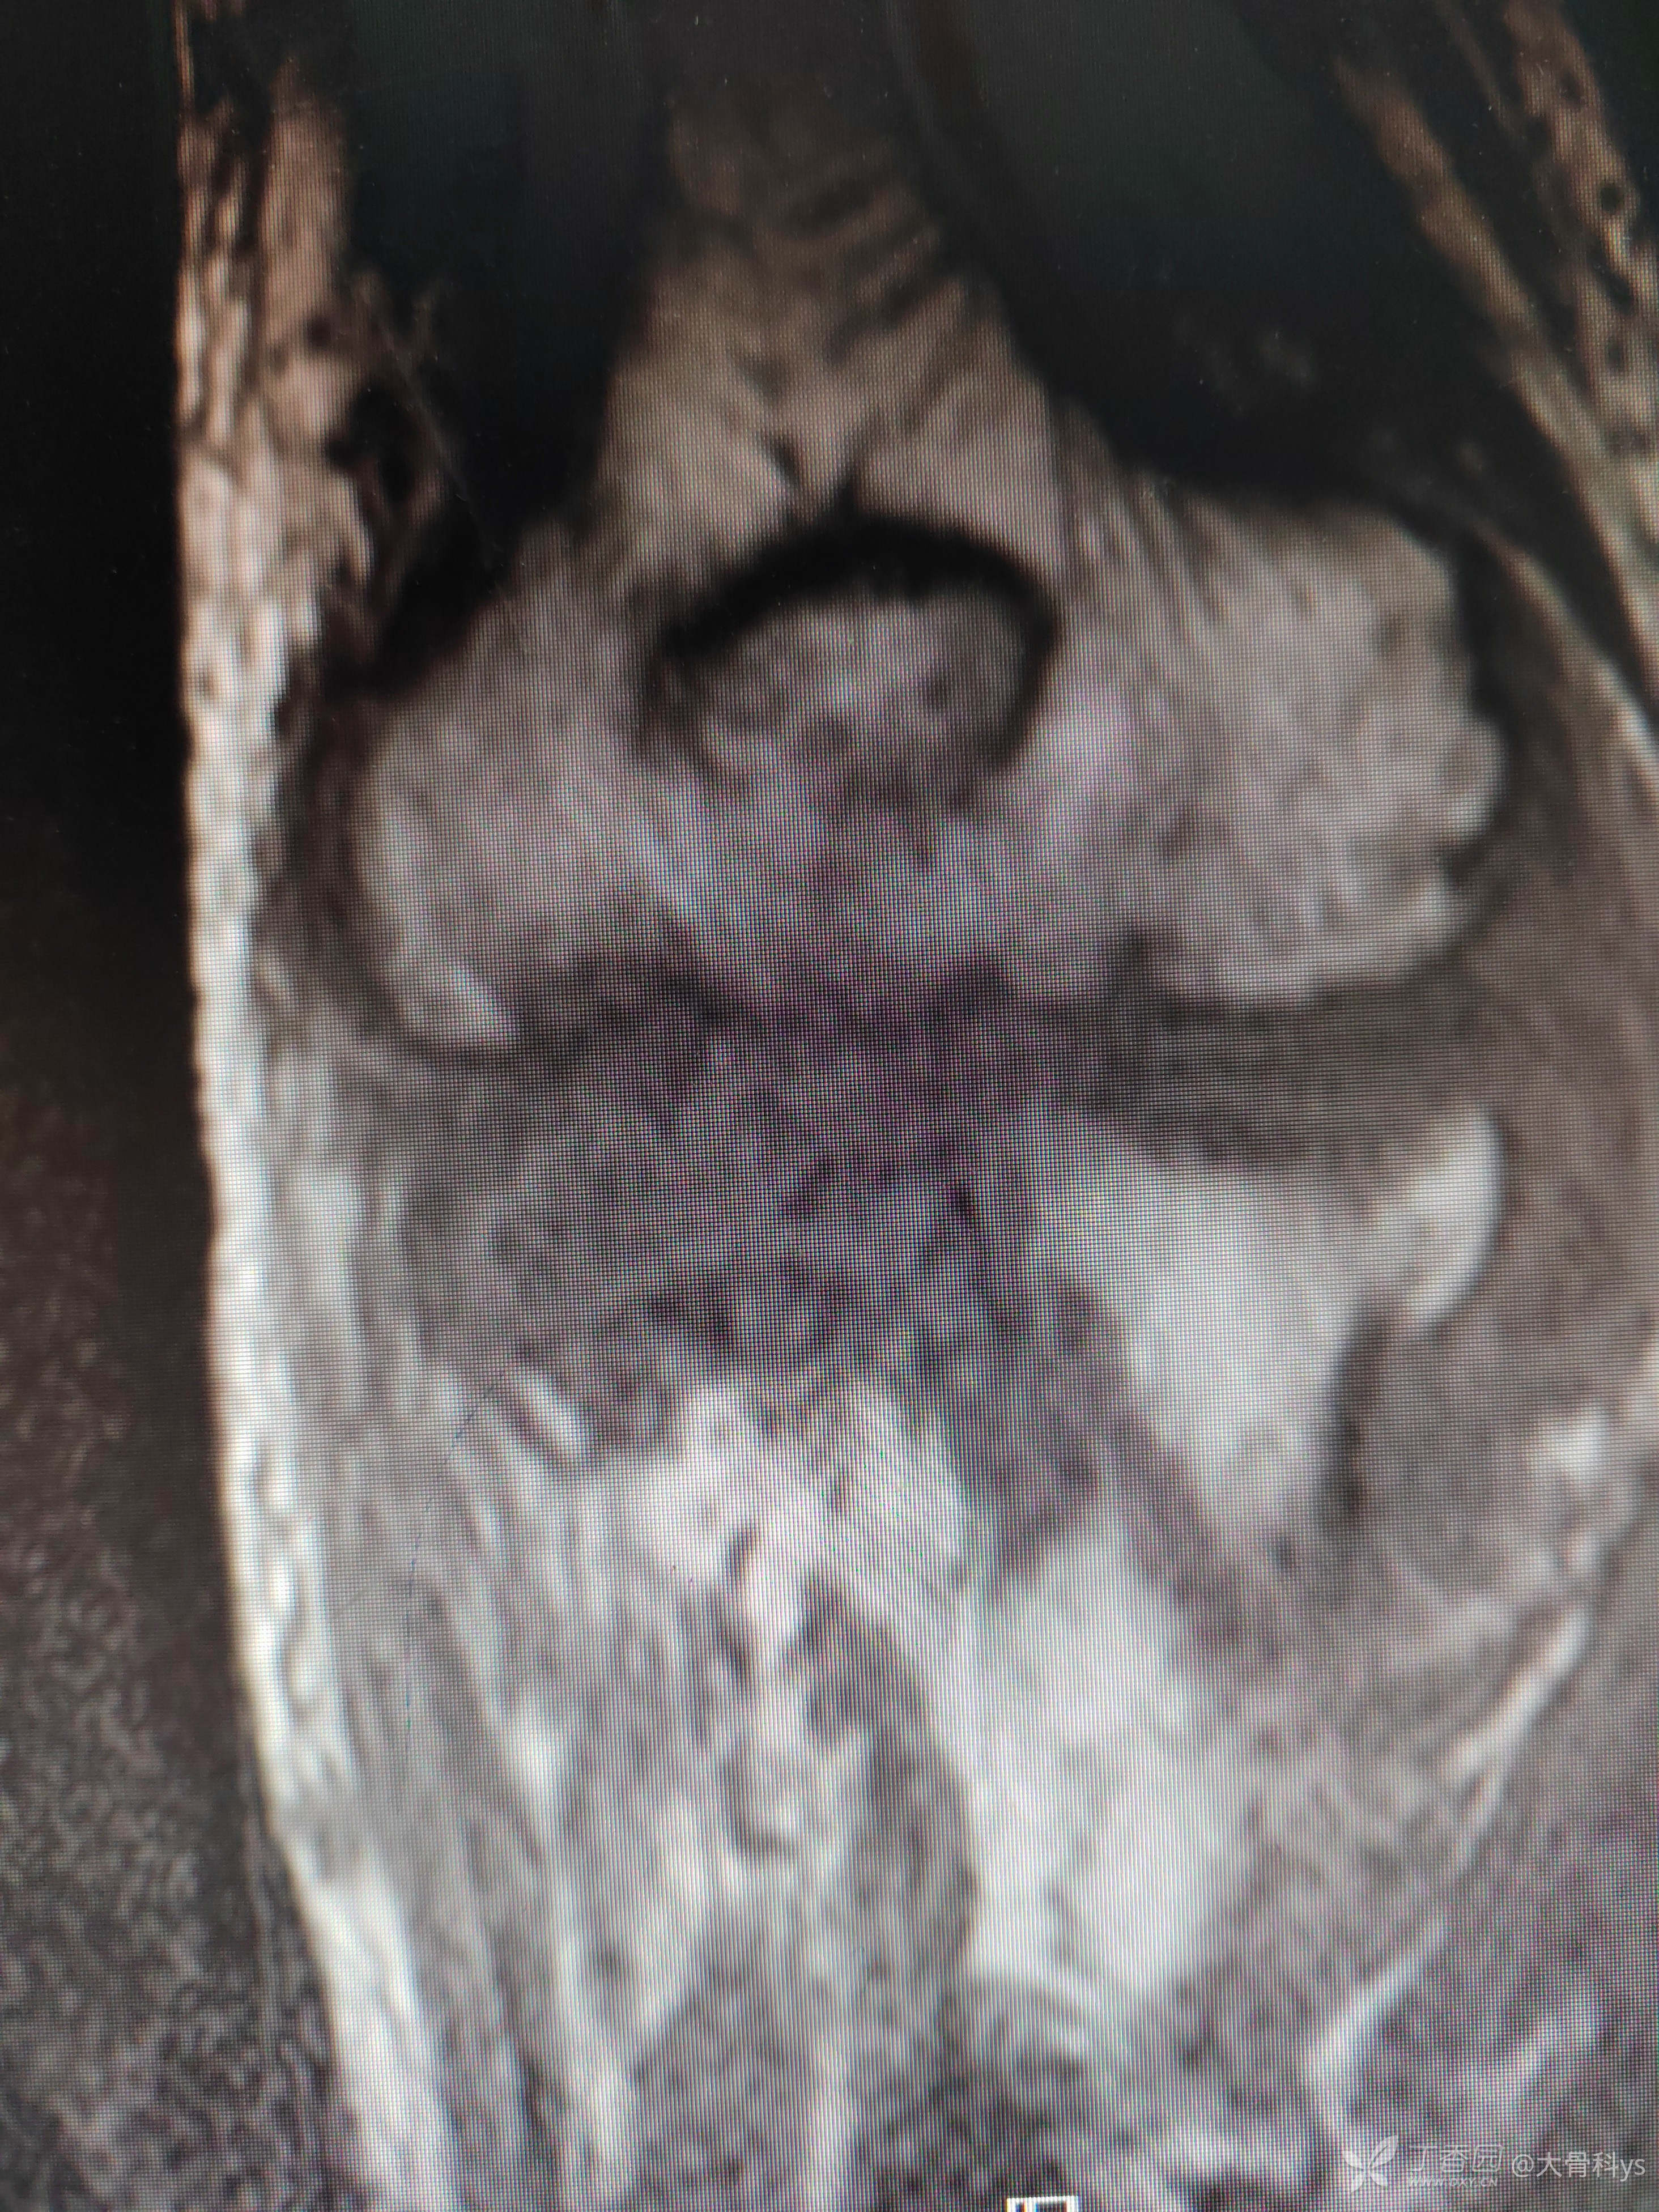

影像学资料

考虑肘关节结核,行关节腔清理+骨髓炎病灶清除+负压封闭引流术。病灶组织再次培养,病灶组织结核杆菌培养,找抗酸杆菌,结核杆菌核酸及利福平耐药检测结果暂未回报。